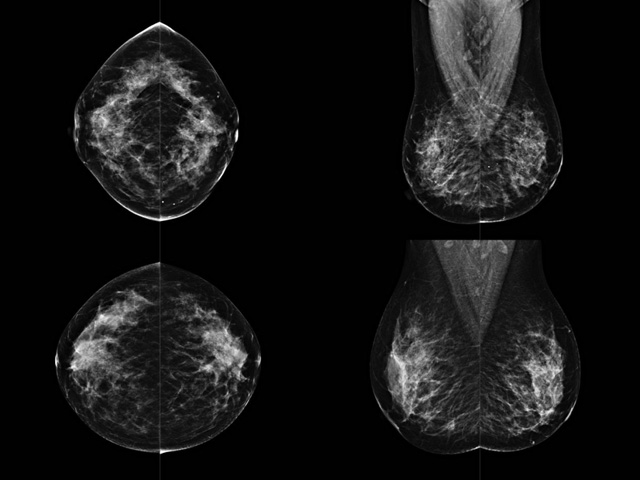

乳房检查时候要注意一些细节,需要更深入的了解这样才能使检查更准确。乳腺DR是乳腺癌的筛查诊断工具设备。是乳房方面检查的重要影像方法。它可以临床检查出早期的乳腺癌??梢耘卸狭夹远裥浴R蛭梢约觳槌鲈缙诘牟”?。对良性恶性检查的准确率达到90%以上。发病高峰年龄为45岁到54岁。50岁检查出来乳腺癌病患,可以让死亡率下降3成。所以30-40岁女性每年做一次乳腺DR检查。40岁以上就一年两次。如果家族史有乳腺癌的30岁以下也需要做检查。清晰显示乳腺各层组织严重的乳腺增生,乳腺炎,乳腺外伤也建议1年检查一次。极大提高了早期乳腺癌的敏感度和诊断率。

大角度、高质量的乳腺检查,可以让女性带来身体健康安全。为医生提供了高清影像数据。乳腺检查时候各个部位影像显示出来。白色乳腺导管跟纤维结缔组织。模糊的是脂肪。病变一般是不透明的白色。有需要放大来检查。乳腺DR没有重叠伪影。辐射剂量更少。因为乳腺癌发病每年都有所提高,对女性都造成了严重的身体健康危害。早做检查早治疗是不可忽视的举措??梢源蟠蟮慕档?/span>死亡率。保证身体健康。一般检查避开经期,来完7天左右是最佳的检查时间。绝经的女性就没有要求。孕妇不参加乳腺DR检查, 6个月内准备妊娠的妇女也不宜行此检查。